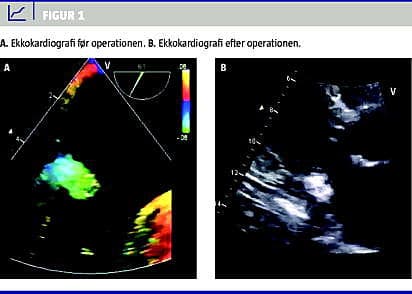

En 55-årig overvægtig ( body mass index: 39 kg/m 2 ) dansk kvinde med hyperlipidæmi (totalt kolesterolniveau: 6,7 mM; højdensitetslipoproteinniveau: 1,2 mM; lavdensitetslipoproteinniveau: 4,7 mM) og hypertension opsøgte egen læge pga. dyspnø og nærsynkoper. Hun var tidligere ryger (20 pakkeår), begge forældre havde haft IHD, hun var ikke diabetiker (glykeret hæmoglobin (HbA 1c ): 6,1%), ikke nyresyg (kreatinniveau: 55 mikroM), havde ikke hyperkalæmi (P-Ca 2+ -niveau 1,26 mM) og var ikke eosinofil (0,4 × 10 9 /l eosinofile leukocytter). Patientens praktiserende læge henviste hende til en privatpraktiserende kardiolog, der udførte en transtorakal ekkokardiografi, hvorved der blev afsløret en tumor i venstre atrium i hjertet, hvilket kardiologen havde mistanke om var et myksom. Patienten blev derfor henvist til yderligere udredning på en kardiologisk afdeling. Her fremgik det, at hun ud over dyspnø og nærsynkoper led af ekstrem træthed. Ved en ny transtorakal ekkokardiografi på hospitalet fandt man en venstre ventrikel-uddrivningsfraktion på 60% og ingen signifikant valvulopati. Ved en transøsofageal ekkokardiografi blev en tumor, der målte 2,4 × 2,4 cm, lokaliseret i venstre atrium (Figur 1 A). Ved en koronararteriografi sås en mindre forsnævring på right coronary artery 1 og snorede arterier, men ellers normale forhold. Ved koronararteriografien blev der ikke afsløret nogen signifikante karstenoser.

Patienten blev fra den kardiologiske afdeling henvist til en thoraxkirurgisk klinik med henblik på tumorexcision og eventuel plastik på mitralklappen. Hun fik foretaget subakut operation med brug af hjerte-lunge-maskine. Højre atrium blev åbnet, og atrieseptum blev incideret, for at man kunne få adgang til venstre atrium. Den 3 × 3 × 5 cm hårde, knoldede tumor lå indlejret i venstre atriums væg lige over mitralklappen, dog uden at involvere denne. Totalresektion var umuligt, hvorfor tumorkapslen blev delvist fjernet (Figur 1B), og indholdet, der blev beskrevet som 30 ml homogent ateromatøst materiale, blev udtømt. Det ateromatøse materiale blev sendt til cytologi, immuntypning samt dyrkning og resistensbestemmelse. Der blev ikke fundet indikation for udskiftning af mitralklappen. Den postoperative rekonvalescensperiode var, fraset pleuraeffusion hhv. 27 og 30 dage efter udskrivelsen, ukompliceret.